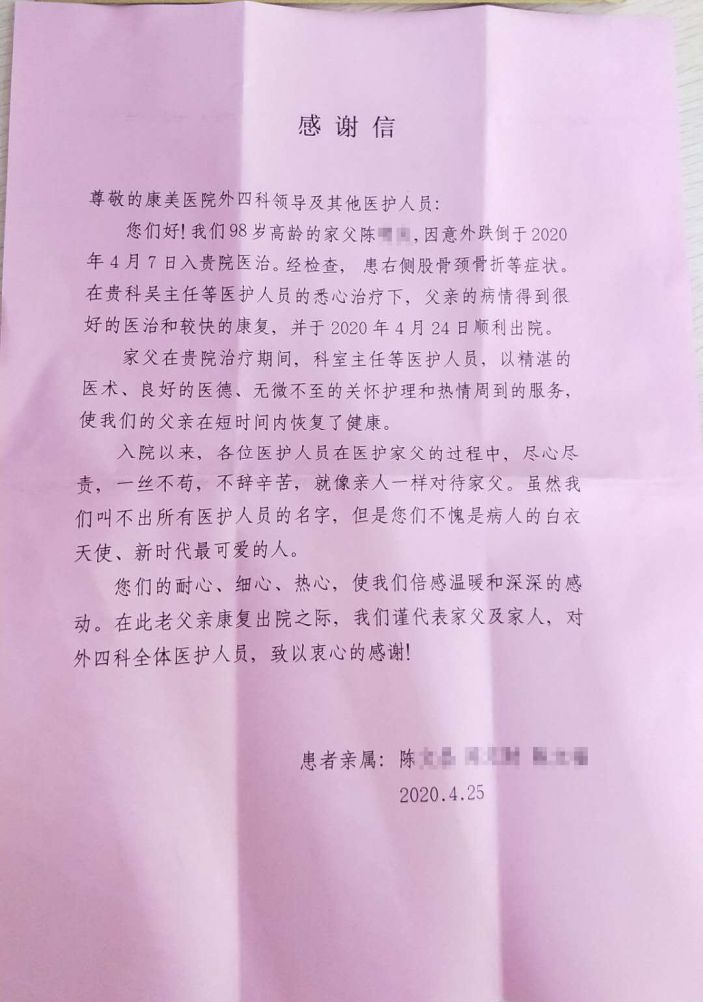

考慮到超高齡患者的基礎疾病多,術後骨科通過與ICU攜手合作,積極對症治療,最終再次成功打破“禁區”,患者順利康複出院,得到了患者家屬的高度贊揚。